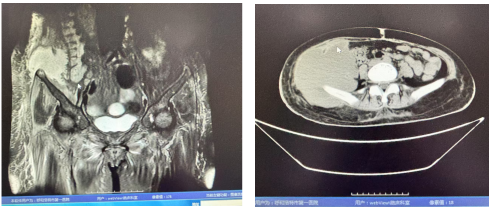

直到2024年12月4日,张某被紧急送至我院急诊。腹部CT检查显示右侧髂骨周围存在异常囊性肿块影,随后被收治入院。入院时,她高烧、呼吸急促、血压低、重度贫血貌,右侧腰腹部大面积皮肤漫肿且有明显波动感。经穿刺探查,涌出黄绿稀薄且恶臭的脓液,最终确诊为坏死性筋膜炎。